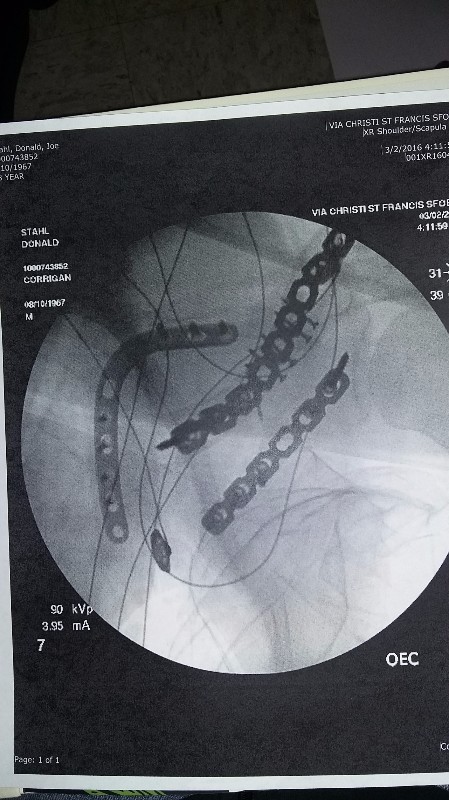

As many know, my dad (don stahl) and his girlfriend were on his motorcycle when they hit a deer February 27th. I am his daughter, and I'm asking for help for them. He is home safe and trying to heal after two surgeries to fix his broken scapula and clavicle. However, his girlfriend has a long road ahead suffering head trauma. With insurances fighting over coverage, fmla not paying enough, and no return to work until healed, he's looking at more then just losing his house. He has already had to sell his beloved mustang, but that doesn't begin to cover his costs. My dad needs our help friends and family. Look around, there are not many like him around. He's always willing to help people, cost not being a matter, payment not a problem. All he generally asks for from anyone is good company. It's our time to help him, please.

As many know, my dad (don stahl) and his girlfriend were on his motorcycle when they hit a deer February 27th. I am his daughter, and I'm asking for help for them. He is home safe and trying to heal after two surgeries to fix his broken scapula and clavicle. However, his girlfriend has a long road ahead suffering head trauma. With insurances fighting over coverage, fmla not paying enough, and no return to work until healed, he's looking at more then just losing his house. He has already had to sell his beloved mustang, but that doesn't begin to cover his costs. My dad needs our help friends and family. Look around, there are not many like him around. He's always willing to help people, cost not being a matter, payment not a problem. All he generally asks for from anyone is good company. It's our time to help him, please.